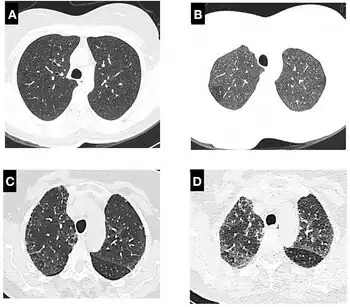

A chest X-ray or CT is necessary to differentiate between pneumonitis and pneumonia of an infectious etiology. Some degree of pulmonary fibrosis may be evident in a CT which is indicative of chronic pulmonary inflammatory processes. Diagnosis of Pneumonitis is often difficult as it depends on a high degree of clinical suspicion when evaluating a patient with a recent onset of a possible interstitial lung disease. In addition, interpreting pathologic and radiographic test results remains a challenge to clinicians. Pneumonitis is often difficult to recognize and discern from other interstitial lung diseases.[7]

- High-Resolution Computed Tomography (HRCT) consistent with pneumonitis

Clinical tests include chest radiography or (HRCT) which may show centrilobular nodular and ground-glass opacities with air-trapping in the middle and upper lobes of the lungs. Fibrosis may also be evident. Bronchoalveolar Lavage (BAL) findings coinciding with pneumonitis typically include a lymphocytosis with a low CD4:CD8 ratio.[7][12]

Reticular or linear patterns may be observed in diagnostic imaging.[7] Pneumonitis may cause subpleural honeycombing, changing the shape of the air spaces in an image, which may be used to identify the respiratory disease.[7] The interlobular septa may also thicken and indicate pneumonitis when viewed on a scan.[7]

Since pneumonitis manifests in all areas of the lungs, imaging such as chest x-rays and Computerized tomography (CT) scans are useful diagnostic tools.[3] While pneumonia is a localized infection, pneumonitis is widespread.[3] A spirometer may also be used to measure pulmonary function.